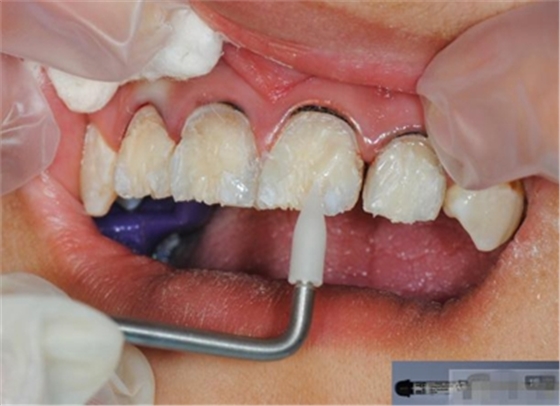

【分層堆塑】

A4本質(zhì)堆塑

Dr.Vanini建議如果牙醫(yī)選色有疑惑的話,最好應(yīng)用顏色深一些的牙本質(zhì)樹脂。

A3本質(zhì)堆塑

發(fā)育葉制作

白堊斑

切端琥珀色制作

A3頸部堆塑

涂布防氧化劑

充填初步完成

【初步修整】

對(duì)于唇面,首先使用火焰狀車針進(jìn)行修整,一般不使用輪狀車針修整線角

微細(xì)的表面結(jié)構(gòu)最后使用鎢鋼拋光車針成形的。